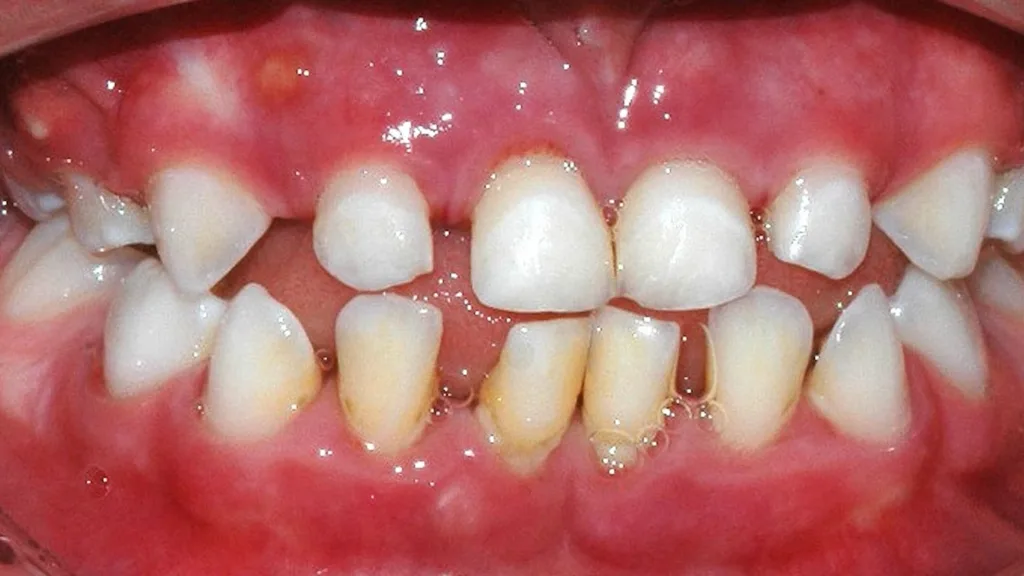

Im Gegensatz dazu existieren eine Reihe seltener Syndrome, bei denen betroffene Personen unabhängig von klassischen Risikofaktoren eine schwere parodontale Destruktion entwickeln. Seltene Syndrome sind (meist) genetisch bedingte Erkrankungen, die durch eine charakteristische Kombination klinischer Symptome gekennzeichnet sind und gemäß europäischer Definition eine Prävalenz von weniger als 1 pro 2.000 Personen aufweisen. In der Parodontologie ist eines der bekanntesten Beispiele das autosomal-rezessiv vererbte Papillon-Lefèvre-Syndrom, das durch eine rasch-progrediente Parodontitis im Kindesalter sowie durch palmoplantare Hyperkeratosen der Hände und Füße gekennzeichnet ist; ursächlich sind Mutationen im Cathepsin-C-(CTSC-)Gen (Abb. 1, Abb. 2).

Das Papillon-Lefèvre-Syndrom (PLS) ist, wenn alle Symptome ausgeprägt sind, durch die generalisierte Parodontitis im Milchgebiss in Kombination mit palmoplantaren Hyperkeratosen klinisch leicht zu diagnostizieren [12]. Allerdings gibt es auch Fälle, in denen nur die Hautveränderungen oder die Parodontitis auftreten. Durch die autosomal-rezessive Vererbung tritt PLS nur auf, wenn beide Allele – das mütterlich und das väterlich vererbte Allel – eines Gens defekt sind. Das können homozygote Mutationen sein, also zwei idente Mutationen, wenn die Eltern einen Verwandtschaftsgrad aufweisen, oder auch unterschiedliche Mutationen im Cathepsin-C-Gen, selten durch Neumutationen. Die Eltern des Kindes als Träger eines einzelnen defekten Allels zeigen typischerweise keine Symptome des PLS. Trotzdem können sie aufgrund der hohen Prävalenz von einer allgemeinen Parodontitis betroffen sein. Die genetische Diagnose stützt sich auf die klinische Verdachtsdiagnose und wird durch den Nachweis pathogener Mutationen im Cathensin-C-Gen gesichert. Die Eltern als Überträger der Mutationen sollen in der Regel in die genetische Analyse mit einbezogen werden.